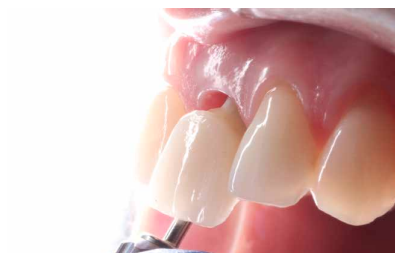

Conclusiones: La rehabilitación sobre implantes en situaciones de pérdida dental en el sector anterior estético y en especial, en pacientes jóvenes, requiere un plan de tratamiento multidisciplinar en cuanto a la extracción del diente y colocación del IOI en la posición tridimensional correcta, existiendo diferentes aspectos a tener en cuenta para ello, especialmente el remanente óseo residual, la posición del margen gingival, así como la preservación y acondicionamiento de los tejidos duros y blandos periimplantarios mediante injertos y un manejo correcto de una prótesis provisional hasta conseguir un perfil de emergencia y contorno gingival ideal antes de la corona definitiva

Conclusions: Rehabilitation on implants in situations of tooth loss in the aesthetic anterior sector, especially in young patients, requires a multidisciplinary treatment plan in relation to tooth extraction and placement of the OII in the correct three-dimensional position. There are various aspects to be taken into account, particularly the residual remaining bone, the position of the gingival margin, as well as the preservation and conditioning of the peri-implant hard and soft tissues by means of grafts and proper handling of a provisional prosthesis until an ideal emergence profile and gingival contour is achieved before the final crown.